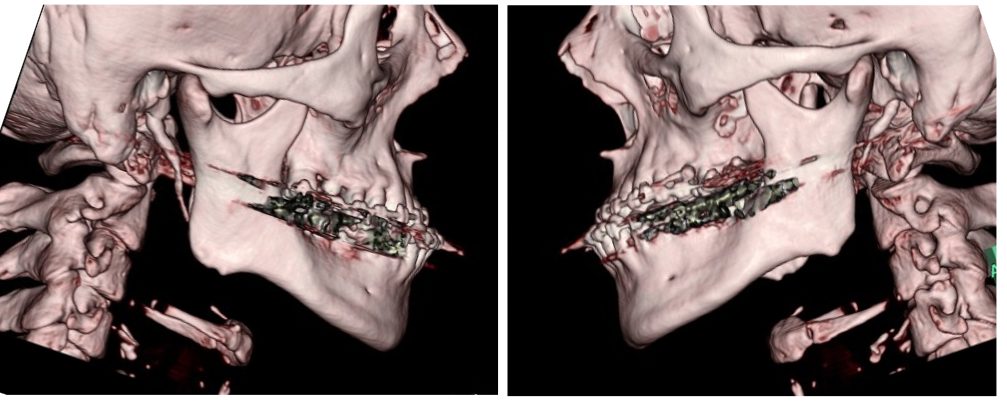

外科矯正治療・インプラント治療・セラミック治療の症例紹介(三隅歯科クリニック)

三隅 賢祐(三隅歯科クリニック)

症例詳細

| 主訴 | 50代男性 右上の歯と歯茎が痛い。どこで噛んでいいのか分からないので夜も眠れない |

| 治療内容 | 外科矯正治療・インプラント治療・セラミック治療を行いました。 |

| 治療費 | 4,500,000円(税込み) |

| 治療期間 | 4年(矯正治療期間 3年) |

| 治療回数 | 60回 |

| 想定されたリスク | 顎骨の変形があったので、全身麻酔下による外科処置が必要になり、身体的、精神的負担が増す可能性がありました。 清掃状況によっては矯正中にむし歯が発生するリスクがありました。 |